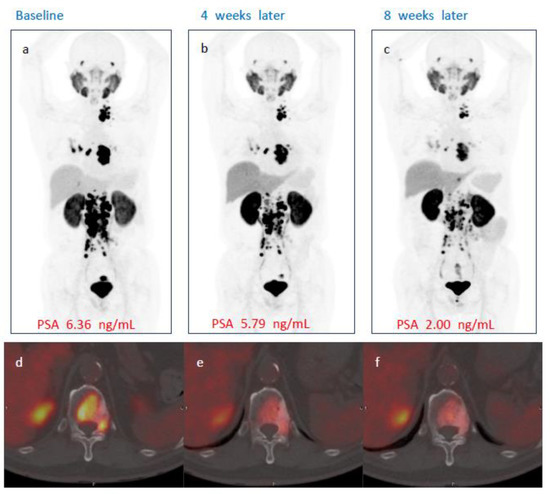

3.5. Radiological Assessment